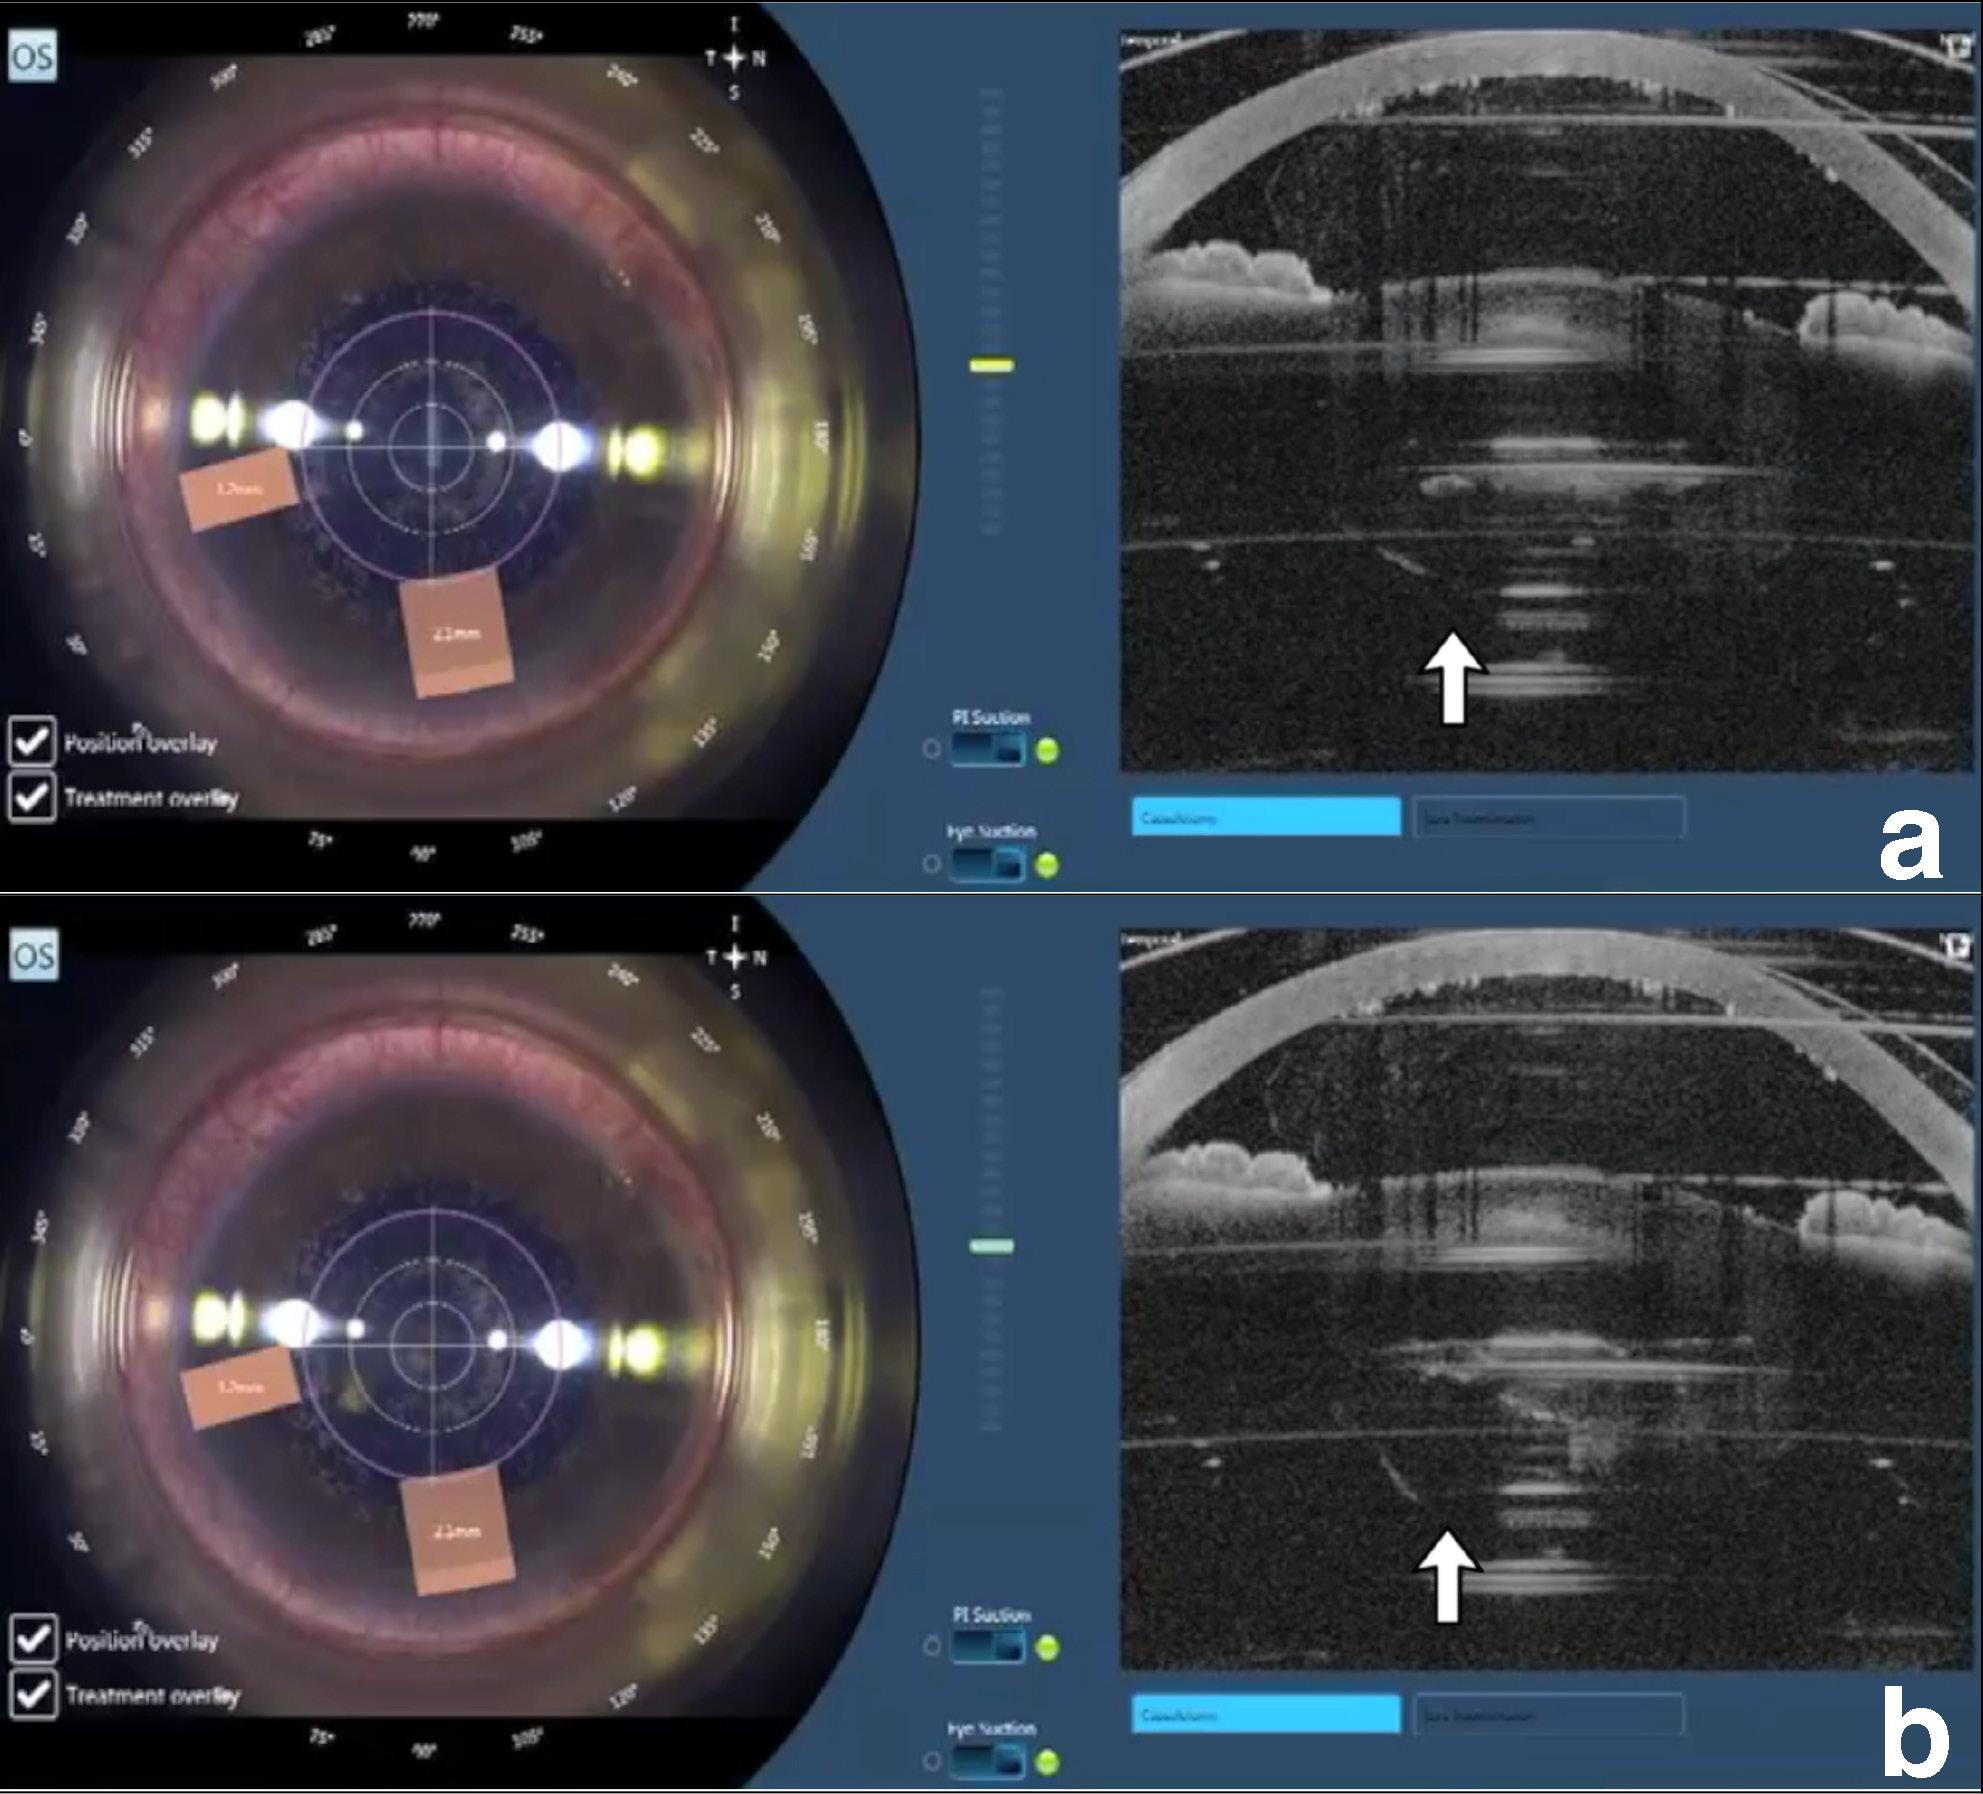

L’occhio si inclina (tilting) subito dopo la procedura di docking o dopo la capsulotomia. In questo caso il pericolo per la capsula posteriore è evidente, poiché il chirurgo può non rendersene conto e procedere comunque con la frammentazione laser che può tagliare la capsula posteriore. Particolare attenzione va riservata quando si sceglie una procedura di “soft docking”, la quale più facilmente permette che condizioni come questa si verifichino, in associazione a ridotta zona posteriore non trattata, ad esempio di soli 0.5 mm (Figura 1).

La concussione della capsula posteriore può essere diffusa all’intera capsula, come mostrato in precedenza, o localizzata in una sua porzione. Questo fenomeno transitorio è solitamente localizzato nella porzione centrale della capsula posteriore, ma per i meccanismi esposti in precedenza, tale concussione può avvenire in maniera isolata anche in periferia. Ciò si può verificare ad esempio in quelle condizioni in cui la cataratta presenta durezza disomogenea e a condizione che la pupilla e l’area di frammentazione siano sufficientemente grandi (Figura 4).

Figura 1. Occhio inclinato dopo procedura docking. Figura 2. Piccoli movimenti della capsula posteriore si possono spesso osservare in corrispondenza del primo piano di applicazione del laser per frammentare la cataratta.

Figura 4. (a-b). Composita che mostra diversi momenti di applicazione del laser per frammentare una cataratta con consistenza disomogenea: a) inizio della frammentazione, la capsula posteriore rimane in sede; b) la freccia indica la porzione di capsula che si è dislocata posteriormente rimanendo integra.